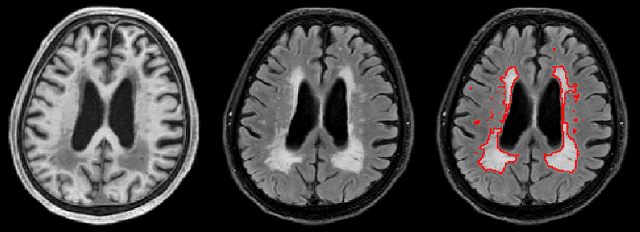

Abstract:Segmentation and quantification of white matter hyperintensities (WMHs) are of great importance in studying and understanding various neurological and geriatric disorders. Although automatic methods have been proposed for WMH segmentation on magnetic resonance imaging (MRI), manual corrections are often necessary to achieve clinically practical results. Major challenges for WMH segmentation stem from their inhomogeneous MRI intensities, random location and size distributions, and MRI noise. The presence of other brain anatomies or diseases with enhanced intensities adds further difficulties. To cope with these challenges, we present a specifically designed fully convolutional neural network (FCN) with residual connections to segment WMHs by using combined T1 and fluid-attenuated inversion recovery (FLAIR) images. Our customized FCN is designed to be straightforward and generalizable, providing efficient end-to-end training due to its enhanced information propagation. We tested our method on the open WMH Segmentation Challenge MICCAI2017 dataset, and, despite our method's relative simplicity, results show that it performs amongst the leading techniques across five metrics. More importantly, our method achieves the best score for hausdorff distance and average volume difference in testing datasets from two MRI scanners that were not included in training, demonstrating better generalization ability of our proposed method over its competitors.